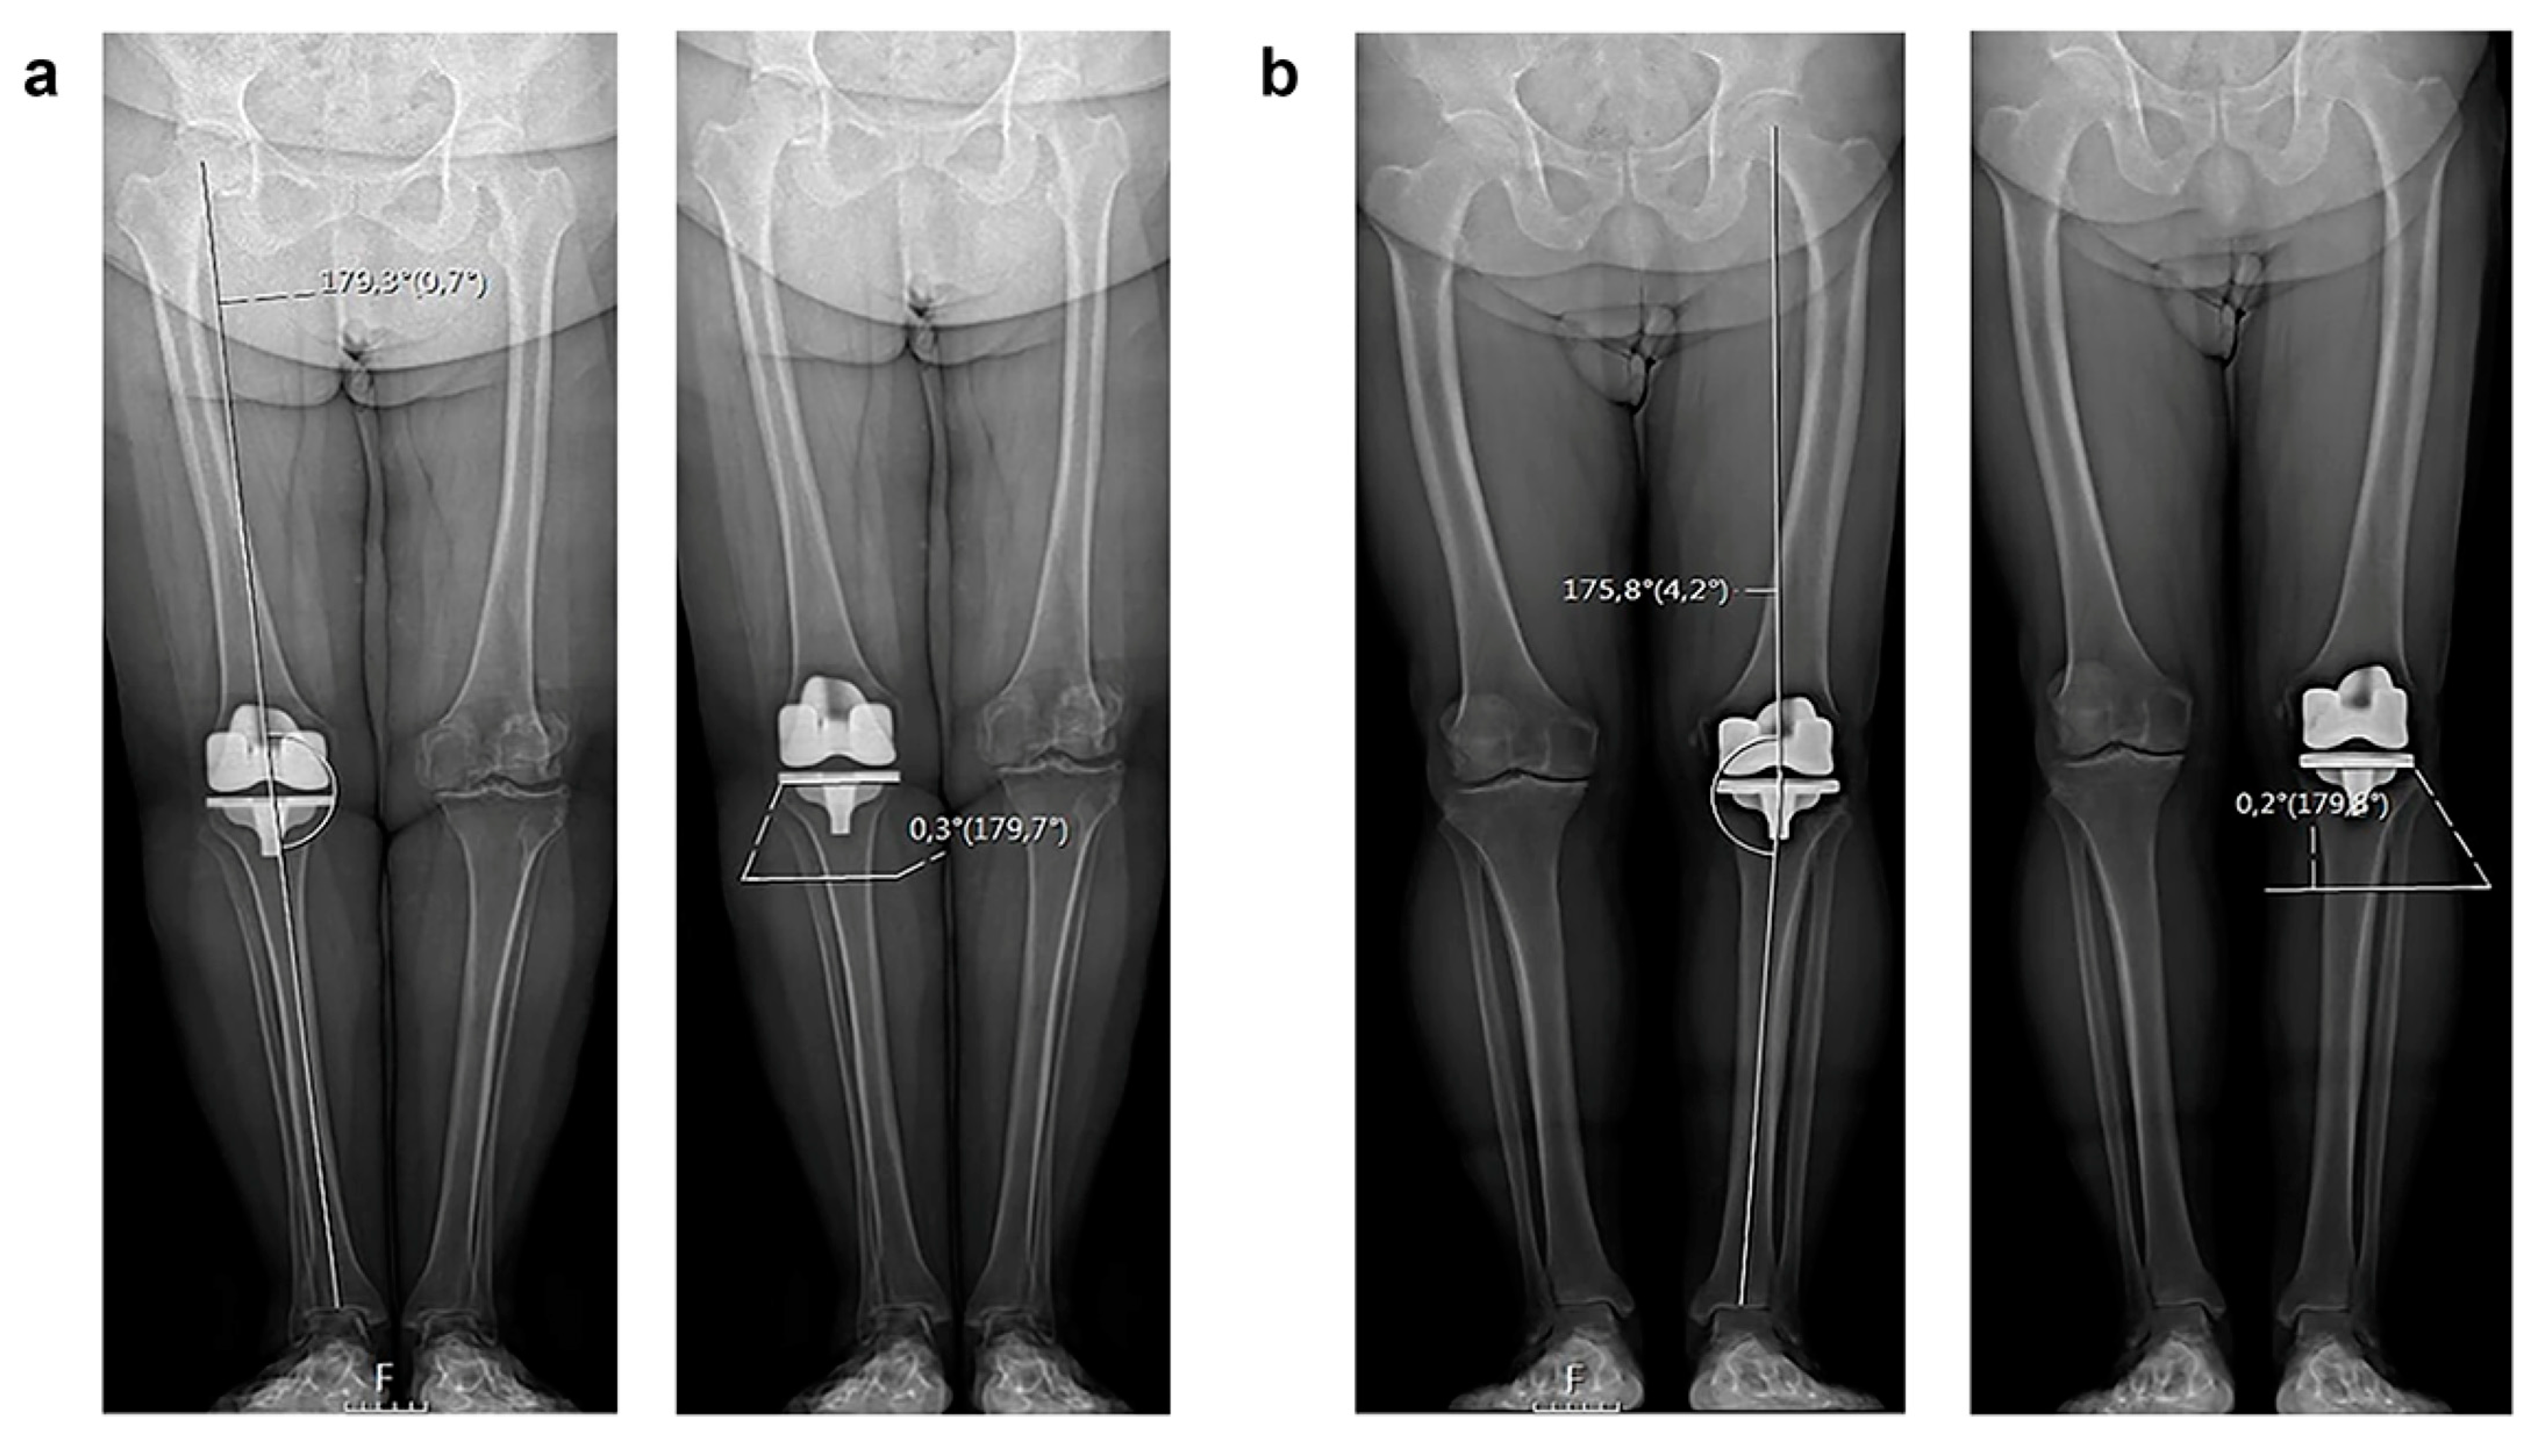

- HKA (hip—knee—ankle) angle;

- mLDFA (mechanical lateral distal femoral angle);

- MPTA (medial proximal tibial angle);

- JLOA (joint line orientation angle).

3.2. Radiological Evaluation